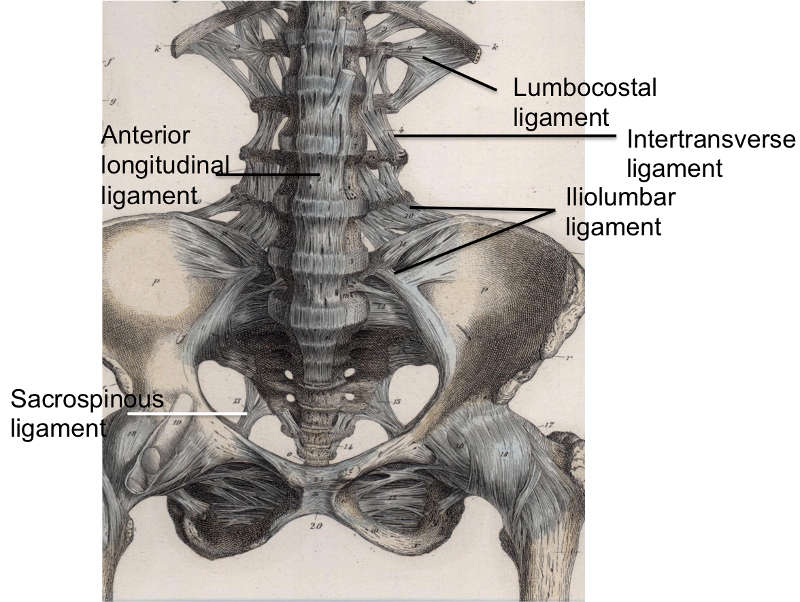

- Lec 3 - Ligaments Diagram | Quizlet

- Ligaments Diagram | Quizlet

- Diagram Of Ligaments | Quizlet